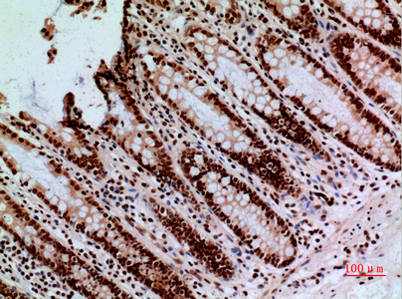

Product name: CacyBP rabbit pAb

Dilutions: Western Blot: 1/500 - 1/2000. IHC-p: 1/100-1/300. ELISA: 1/20000. Not yet tested in other applications.

Immunogen: The antiserum was produced against synthesized peptide derived from the C-terminal region of human CACYBP. AA range:171-220